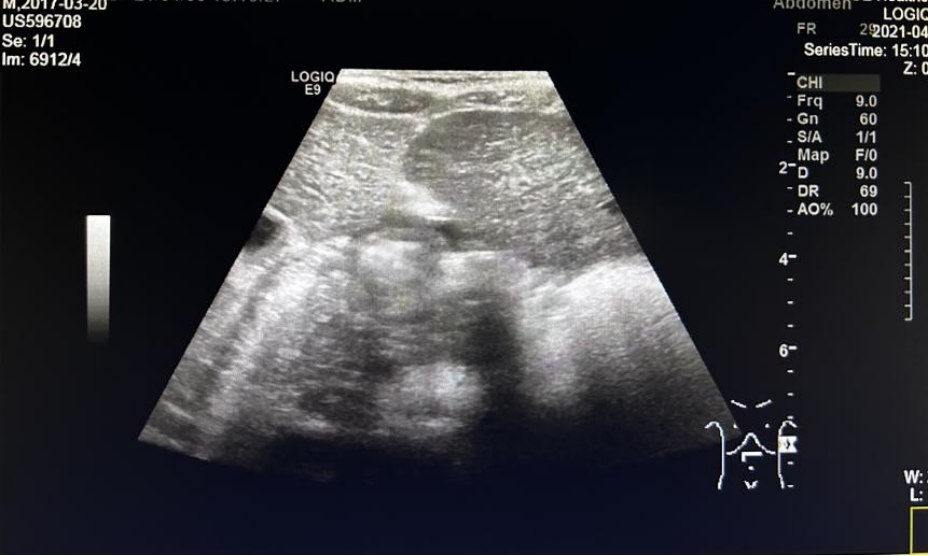

现病史与既往史:初诊1月余前游玩时自诉右下肢疼痛,呈持续性疼痛,性质不详,休息后无法缓解,无发热、腹痛等症状。双侧髋关节MR(2021.1.6)提示“双侧髂骨、坐耻骨、股骨及其骨骺、骶尾椎及所见腰椎广泛骨质破坏,伴周围软组织肿胀”。腹部B超(2021.1.8)提示“右侧后腹膜低回声包块”。既往史无殊。

术后评估:2021.4.6腹部B超未见异常包块。